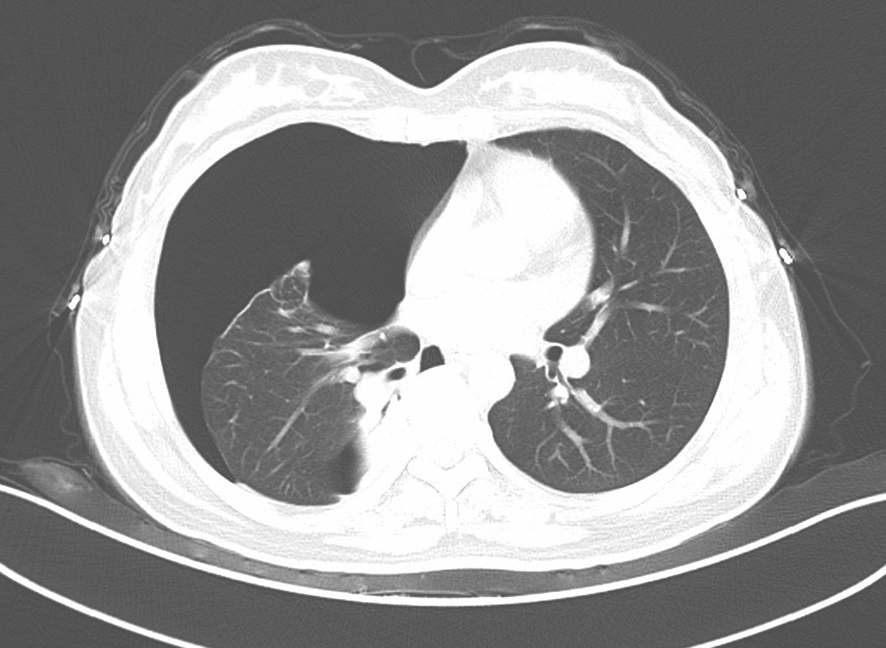

通过CT检查少量的胸腔积液亦能显影。CT的优点还包括通过病灶密度观察可将局限包裹性积液与肺实质病变加以鉴别;强化造影后可较好地显示纵隔、肺门、气管旁淋巴结、肺内肿块及胸膜病变等(图2-13-3)。

图2-13-3 渗出性胸膜炎强化CT